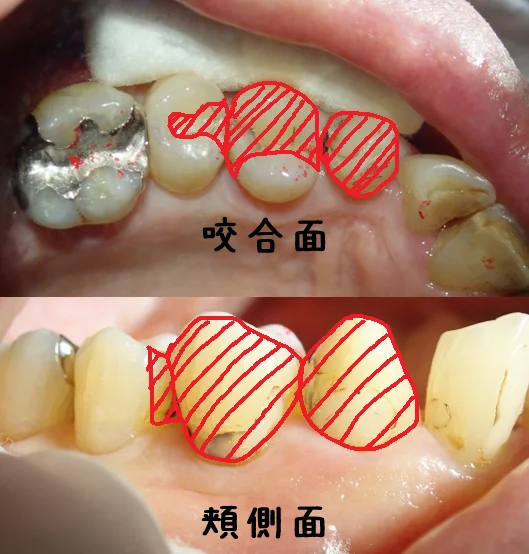

ではまず術前から。

咬合面が上からの図で、頬側面が頬っぺた側から見た図です。

咬む面から頬っぺた側に広範囲に虫歯が出来てしまっています。

この場合、インレーやクラウンでの治療が一般的ですね。